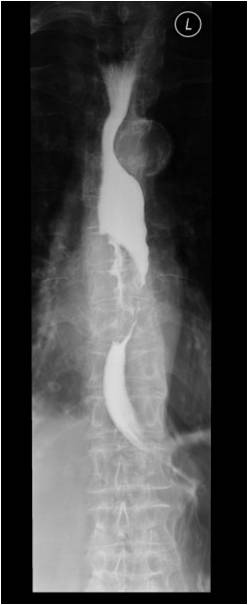

Image

Fig.2.: Achalasia

Radiographic findings: marked dilatation of the esophageal lumen. Luminal diameter can be seriously widened. In advanced cases the tortuous gullet constitutes the mediastinal interface. The cardia shows conical narrowing. The esophageal lumen is filled with undigested food. Opening of the cardia is delayed, emptying is intermittent. The stomach is shrunken. The result is a so called microgaster as the esophagus takes over the stomach’s reservoir function.